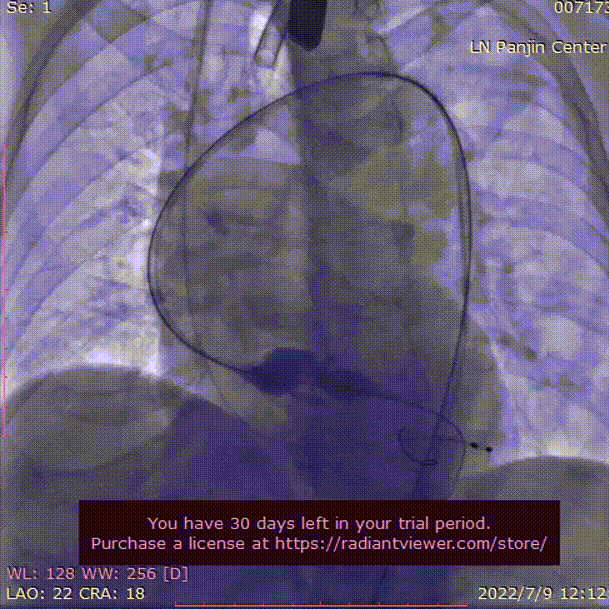

术中影像

主动脉根部造影